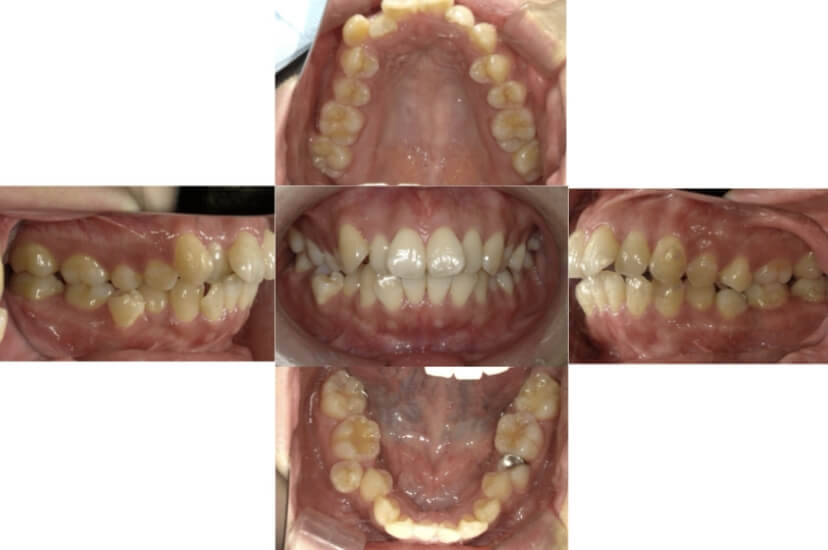

BEFORE

AFTER

上下顎叢生、反対咬合(上下の前歯のガタガタ、若干受け口)のケースです。

装置はラビアル(上下表側)で、上下顎の小臼歯を4本抜歯を行っています。抜歯したスペースを使って、上下の叢生改善と前歯の受け口の改善を行っています。

主訴 前歯のガタガタを治したい。

年齢・性別 45歳 女性

お住まいの地域 神奈川県川崎市

治療方針 抜歯スペースを利用して上前歯の叢生(ガタガタ)の改善と受け口の改善

抜歯部位 上顎左右第一小臼歯、下顎左右第二小臼歯

使用装置 ラビアル(上下表側)、顎間ゴム

治療期間 2年6か月

治療回数 20回

リテーナー クリアリテーナー